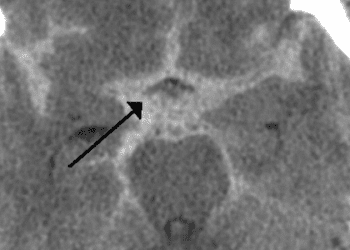

Image: CC Sasha Wolf, wikipedia